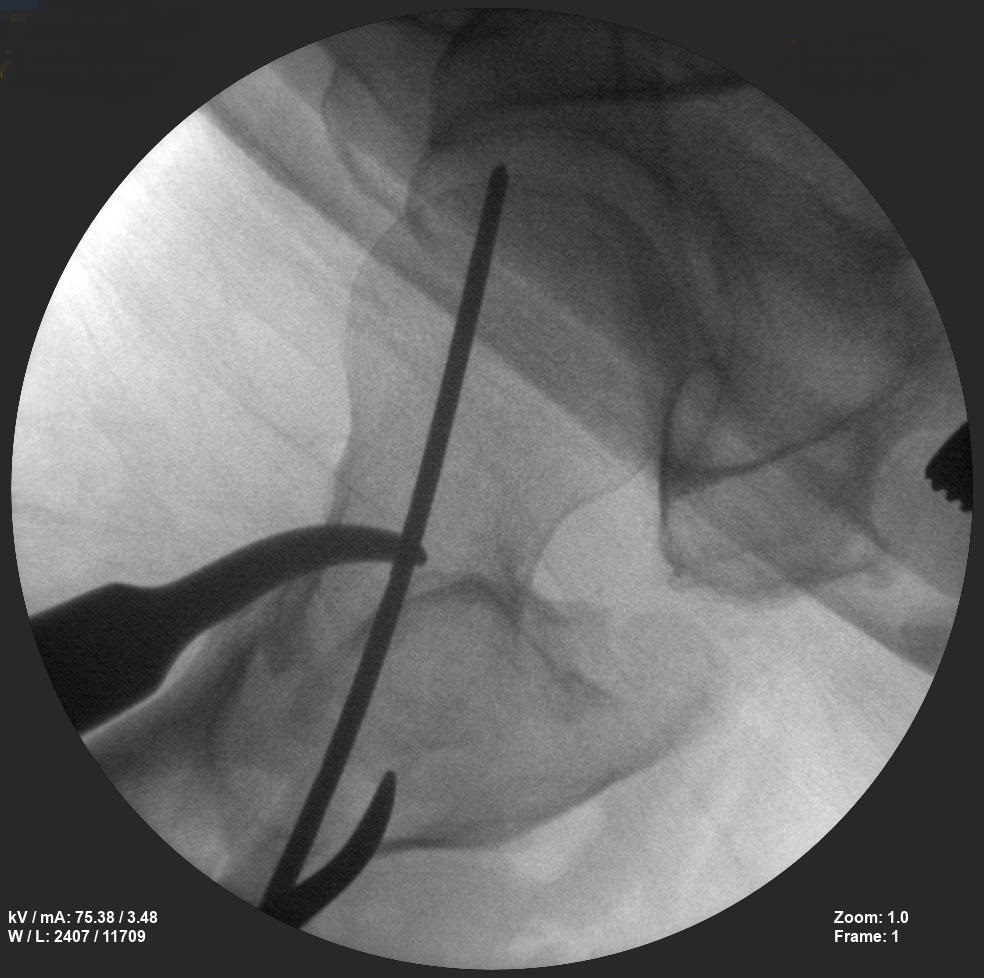

Skan-C plays a critical role in orthopaedic procedures, providing excellent imaging during interventional procedures, and allowing for precise localization and accurate treatment. The ability of Skan-C to offer dynamic visualization of visualization structures enhances patient safety, minimizes complications, and improves the overall effectiveness of orthopedic interventions.

CRIF - Closed reduction internal fixation

ORIF - Open reduction internal fixation